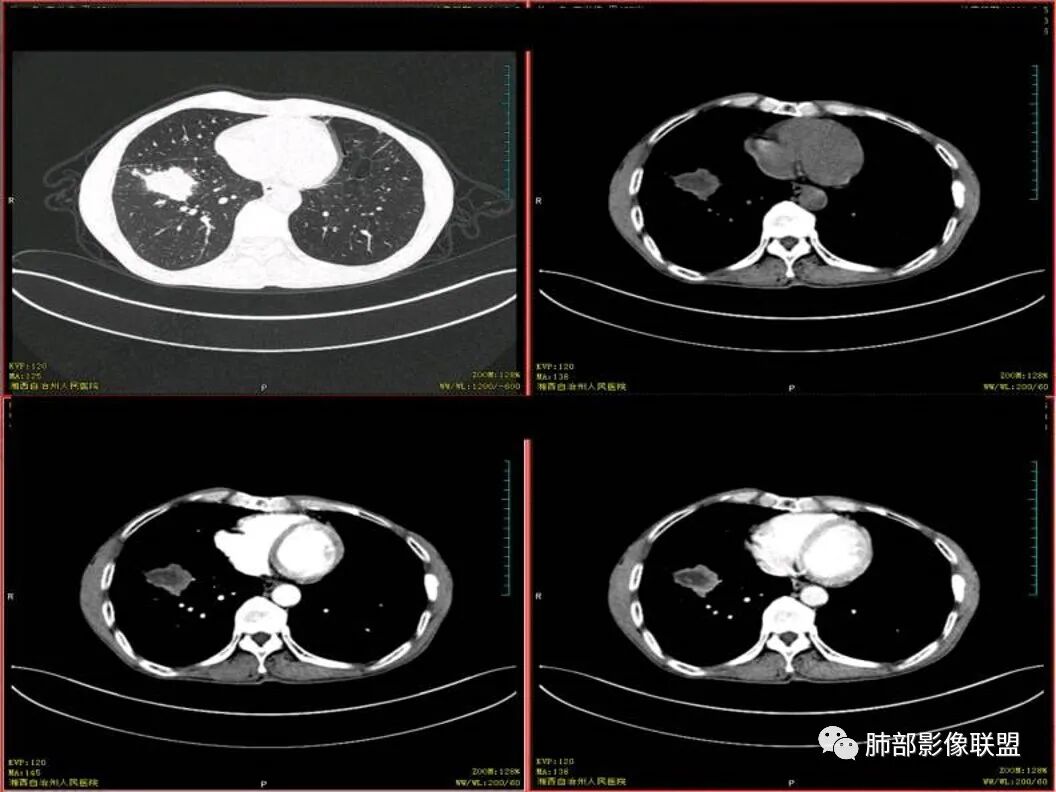

双上肺多发斑片、结节及条索影,边缘清晰,右肺下叶肿块,边缘分叶毛刺,密度不均有坏死,叶间胸膜及侧胸膜牵拉凹陷,斜裂可见六个核桃,周围小叶间隔呈串珠状,纵膈淋巴结肿大坏死,边缘可见钙化,考虑双肺结核,右下肺腺癌。鉴别鳞癌。

患者中年男性,以咳嗽 胸痛就诊

既往有肺结核病史

胸CT可见右肺下叶前基底段占位性病变,病灶周围可见周围不清毛玻璃影,病灶边缘可见分叶,呈膨胀性生长,纵隔窗可见病灶内呈偏心性坏死,增强扫描静脉期强于动脉期,纵隔隆突下淋巴结可见肿大坏死。

诊断考虑肺结核合并肺癌?

男性,咳嗽咳痰,无发热,以往结核并治疗中,两肺有结核背景,淋巴结增大钙化,右肺下叶病灶边缘模糊,内部坏死,坏死区边缘光整,实性部分强化均匀,血管通过截断

诊断:双肺tb+右肺下叶肺癌(鳞癌>腺癌)

双上肺多发病灶,考虑结核(陈旧灶为主),右肺下叶前基底段占位,分叶、毛刺、胸膜牵拉,中央坏死,局部壁不光滑,前基底段支气管未见显示,不均匀强化,病灶远端阻塞性炎症,纵隔淋巴结肿大、融合。综合考虑恶性病变,鳞癌可能大。